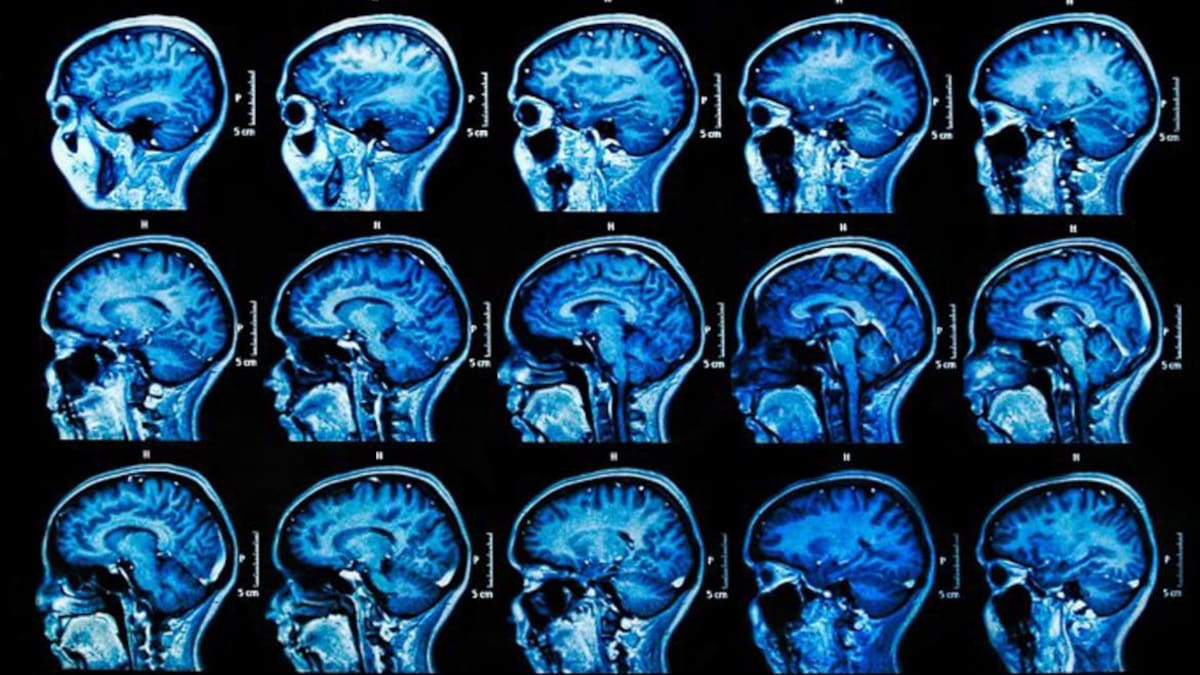

La esclerosis lateral amiotrófica es una enfermedad progresiva del sistema nervioso que afecta a gente de 40 a 70 años, daña y mata todas las neuronas motoras y atrofia todos los músculos.

Todo es consecuencia del daño y muerte de las neuronas motoras, o sea, las que sirven para dar movimiento. El Dr. Alejandro Andersson explicó algunas cuestiones básicas de la enfermedad.

En el sistema nervioso los mensajes los transmiten las neuronas. Las neuronas que reciben estímulos y son el camino de entrada son las sensitivas, las que conectan neuronas entre sí son las asociativas, y las que estimulan un efector como el músculo y son la salida, son las motoras, éstas son las únicas que se comprometen en la esclerosis lateral amiotrófica.

Si las neuronas se dañan, los músculos no reciben más los estímulos de las neuronas motoras, se debilitan y se atrofian. Ocurre con todos los músculos del cuerpo, incluso con los respiratorios.

No se compromete la sensibilidad, la visión, el oído, el gusto, el olfato, la inteligencia ni la capacidad de prestar atención. Se conserva la lucidez aún en las etapas más avanzadas de la enfermedad.